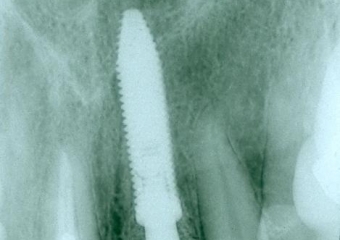

Imagem do dente 21 fraturado

Imagem após extração e instalação de implante e prótese fixa provisória imediata

Raio X com prótese provisória fixa sobre o implante